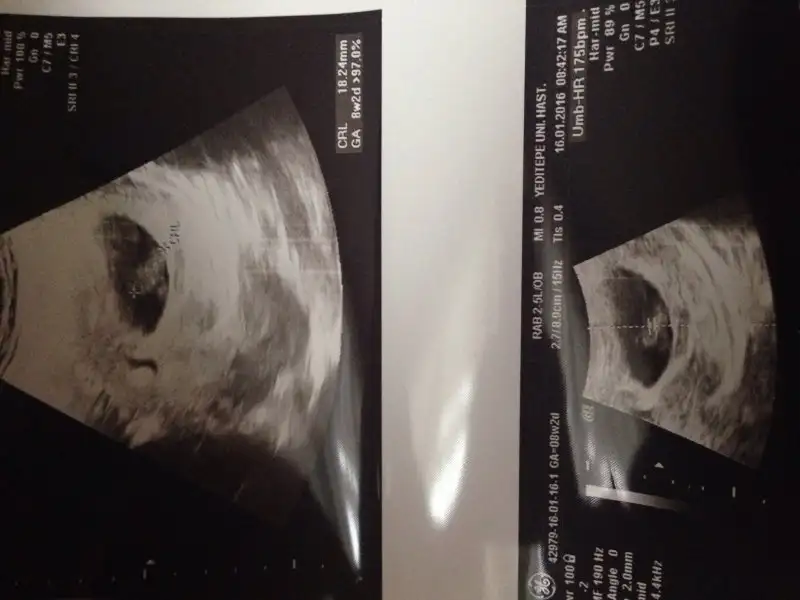

Havalianne__ Havalianne__ rica etsem benim fotoğraflarada bakarmısın ilki alttan 5.hafta diğerleri karından 7. Haftada çekildi merakdan ölüyorum içime sürekli kız diye doğuyor ama kısmet Allah bilir tabii:KK49:

• image.webp

image.webp

9,4 KB · Görüntüleme: 129